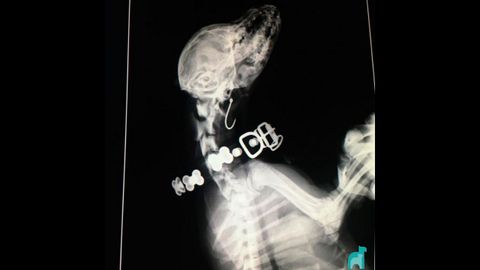

Radiografía de la perra que se tragó un anzuelo

La polémica por los anzuelos abandonados en la playa de San Lorenzo de Gijón aún no ha cesado. Aunque varios dueños de perros han denunciado ya las consecuencias del desamparo de los materiales de pesca, todavía hay cánidos que sufren lesiones por tragarse esos ganchos. El caso más sonado ha sido el de Popper, quien ingirió uno y su operación costó 800 euros, pero no se trata de un hecho aislado. El Hospital Veterinario Asturias de Gijón ha mostrado a través de sus redes sociales una radiografía de una perrita que había engullido un hilo y, por ende, el gancho.

«Después de varias horas, le hicimos una apertura lateral en la garganta, para posteriormente cortar el hilo por la mitad y sacar ambos trozos», explican desde el propio centro veterinario. Además, añaden que «con mucho trabajo y paciencia, todo salió bien» y que, tras la operación, la perrita fue dada de alta y ya se está recuperando en su hogar.